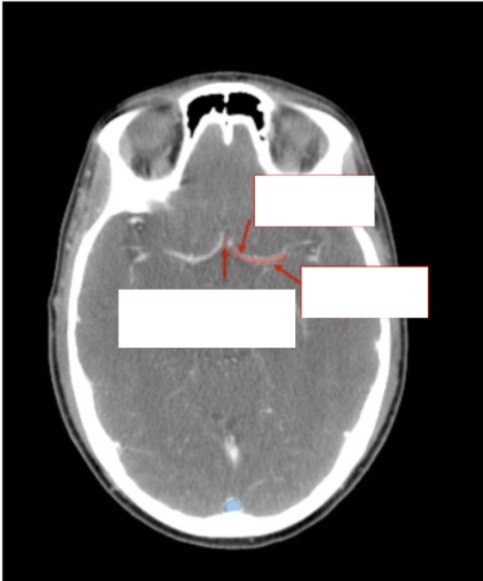

What arteries are these?

Please label the following arteries